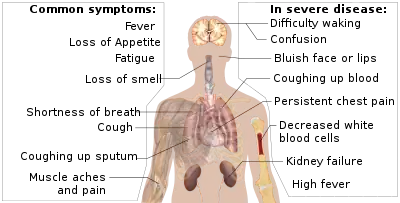

The symptoms of COVID‑19 are variable but often include fever,[7] cough, headache,[8] fatigue, breathing difficulties, loss of smell, and loss of taste.[9][10][11] Symptoms may begin one to fourteen days after exposure to the virus. At least a third of people who are infected do not develop noticeable symptoms.[12] Of those who develop symptoms noticeable enough to be classified as patients, most (81%) develop mild to moderate symptoms (up to mild pneumonia), while 14% develop severe symptoms (dyspnea, hypoxia, or more than 50% lung involvement on imaging), and 5% develop critical symptoms (respiratory failure, shock, or multiorgan dysfunction).[13] Older people are at a higher risk of developing severe symptoms. Some people continue to experience a range of effects (long COVID) for years after infection, and damage to organs has been observed.[14] Multi-year studies are underway to further investigate the long-term effects of the disease.[15]

The symptoms of COVID-19 are variable depending on the type of variant contracted, ranging from mild symptoms to a potentially fatal illness.[36][37] Common symptoms include coughing, fever, loss of smell (anosmia) and taste (ageusia), with less common ones including headaches, nasal congestion and runny nose, muscle pain, sore throat, diarrhea, eye irritation,[38] and toes swelling or turning purple,[39] and in moderate to severe cases, breathing difficulties.[40] People with the COVID-19 infection may have different symptoms, and their symptoms may change over time. Three common clusters of symptoms have been identified: one respiratory symptom cluster with cough, sputum, shortness of breath, and fever; a musculoskeletal symptom cluster with muscle and joint pain, headache, and fatigue; and a cluster of digestive symptoms with abdominal pain, vomiting, and diarrhea.[40] In people without prior ear, nose, or throat disorders, loss of taste combined with loss of smell is associated with COVID-19 and is reported in as many as 88% of symptomatic cases.[41][42][43]

Of people who show symptoms, 81% develop only mild to moderate symptoms (up to mild pneumonia), while 14% develop severe symptoms (dyspnea, hypoxia, or more than 50% lung involvement on imaging) that require hospitalization, and 5% of patients develop critical symptoms (respiratory failure, septic shock, or multiorgan dysfunction) requiring ICU admission.[44] At least a third of the people who are infected with the virus do not develop noticeable symptoms at any point in time.[45][46] These asymptomatic carriers tend not to get tested and can still spread the disease.[46][47][48][49] Other infected people will develop symptoms later (called "pre-symptomatic") or have very mild symptoms and can also spread the virus.[49]